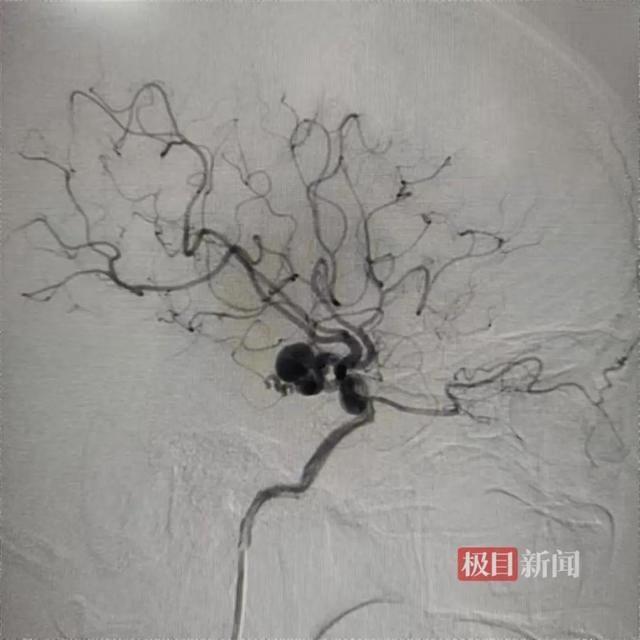

糖糖(化名)颅内的“蛇形动脉瘤”

糖糖(化名)颅内的“蛇形动脉瘤”然而,接诊的神经外科副教授杨海峰发现,糖糖的动脉瘤很少见,且病变处有非常重要的穿支血管,一旦闭塞还会引起偏瘫、昏迷等严重并发症。因此,常规手术都无法安全有效地解决问题。杨海峰教授组织手外科团队讨论,决定采用自体血管移植,在动脉瘤的后段血管上重新建立血液通道,让动脉瘤和病变血管“孤立无援”的治疗方案。通俗地说,就像是河流改道,重新给流经动脉瘤的血流新建一条通道,动脉瘤没有血供之后便毫无威胁,能避免传统手术方式造成的脑梗危险。高难度一站式手术精准“拆弹”1月7日,杨海峰教授团队、手外科陈江海教授团队在手术室和麻醉科的协作配合下,为糖糖实施了“右侧颈外动脉—桡动脉—大脑中动脉”搭桥手术。